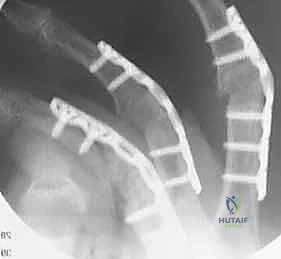

- Tension Band Fixation: This is a biomechanically superior method, often considered the gold standard for small joint arthrodesis.

- Mechanism: It combines parallel Kirschner wires for rotational control with interosseous wiring for compression. The genius of this

- Multiple studies have evaluated the biomechanical advantages of one type of surgical technique versus another in order to establish the most rigid type of fixation that will allow a rapid and complete arthrodesis.

A comparison between the failure load of a Herbert screw and the failure load of a tension band construct showed no significant difference between the two 2 ; the authors concluded that these two methods of fixation have similar biomechanical strength.

A comparison of multiple fixation techniques showed that arthrodesis by screw fixation had a better fusion rate than Kirschner wires, tension band construct, and plate fixation. 10

A comparison of tension band constructs versus Kirschner wire fixation for PIP joint arthrodesis concluded that tension bands provide more rigid fixation. 9